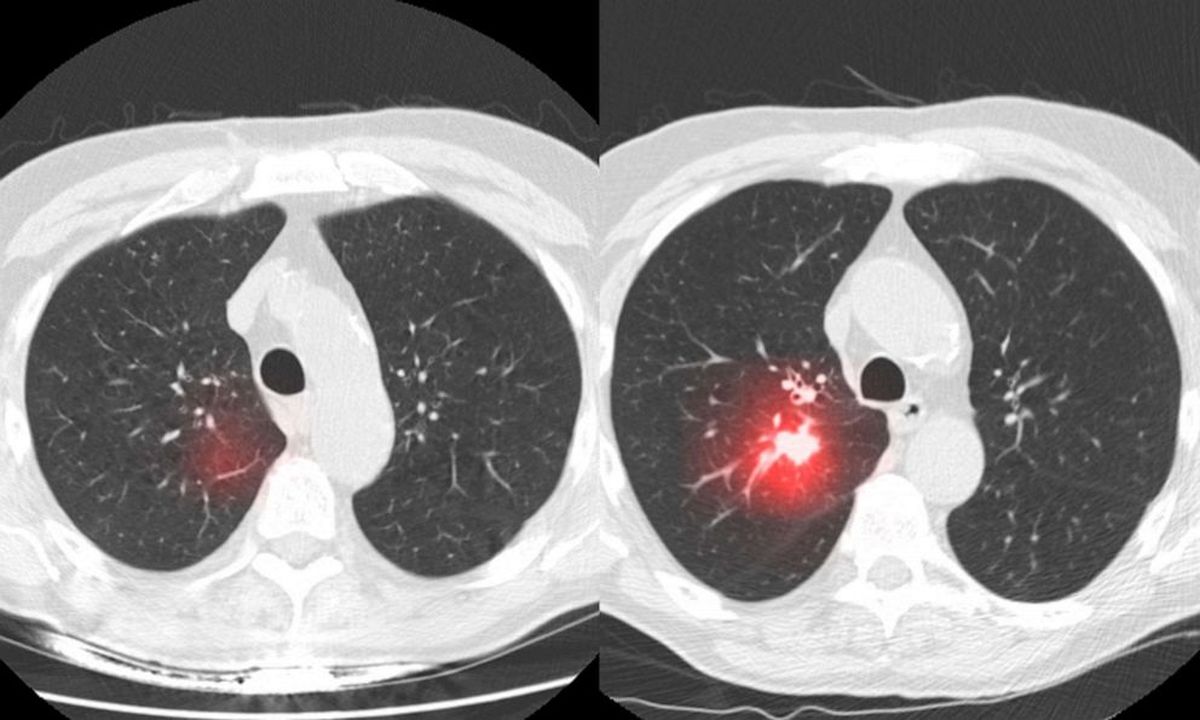

Así fue como nació CHIEF (Fundación para la evaluación de imágenes de histopatología clínica, según sus siglas en inglés), que tras las etapas iniciales de testeo alcanzó un 94 por ciento de efectividad en la detección del cáncer, algo muy superior a los números alcanzados por otras inteligencias artificiales.

CHIEF funciona leyendo diapositivas digitales de tejido de tumores, puede predecir la supervivencia de un paciente de varios tipos de cáncer, y puede señalar características de un tumor que modifican la respuesta del enfermo a diferentes tipos de tratamiento.

Uno de los éxitos más grandes de este modelo es que detectó características de tumores que estaban ligadas a la supervivencia de un paciente, y que eran desconocidas hasta el momento.

CHIEF predijo la supervivencia a largo plazo un 8 por ciento mejor que otros modelos. En los casos de cáncer avanzado, estas predicciones fueron un 10 por ciento más certeras que otras IA. 17 hospitales confirmaron la habilidad de CHIEF predecir la supervivencia de los pacientes.